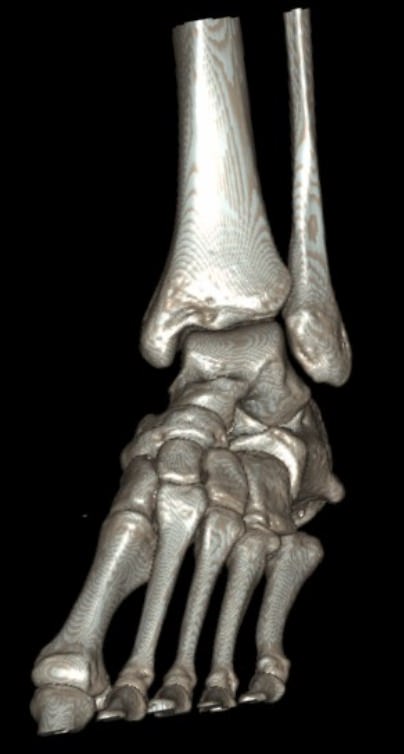

Во время исследования рентгеновская трубка томографа вращается вокруг исследуемой области и производит множество послойных снимков с шагом от 0,5 мм. Полученные снимки поперечного сечения с помощью компьютерной программы могут быть преобразованы в 3D-изображения исследуемого органа. Это позволяет выявлять различные патологические процессы на начальных стадиях и назначать своевременное лечение.

В отличие от обычного рентгена, при котором изображения костных структур накладываются друг на друга, что затрудняет диагностику, компьютерная томография дает возможность увидеть объемную модель сустава, наглядно оценить пространственное соотношение внутрисуставных структур, суставных поверхностей, расположение костных отломков при переломах и травмах. Это особенно важно в ходе подготовки к оперативному вмешательству и в послеоперационном периоде для оценки успешности проведенной операции.